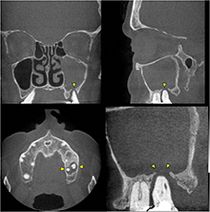

Dentogene Sinusitis der Kieferhöhle links durch eine Entzündung im Bereich einer Zahnwurzelspitze mit Zerstörung des umgebenden knöchernen Kieferhöhlenbodens (Digitale Volumentomographie, DVT)

Die Diagnostik dieser Erkrankung basiert neben der Beschwerdesymptomatik (Nasenatmungsbehinderung, Schmerzen/Druck, Sekretion, Riechminderung) auf der Endoskopie der Nase und der obligaten Schnittbilddiagnostik der Nasennebenhöhlen. Hierzu verfügen wir über die derzeit modernste Diagnostik – die Digitale Volumentomographie (DVT) –, die eine hochauflösende dreidimensionale Darstellung des Geschichtsschädels, der Nasennebenhöhlen und des Oberkiefers bei im Vergleich zur konventionellen Computertomographie deutlich niedrigerer Strahlenbelastung ermöglicht.